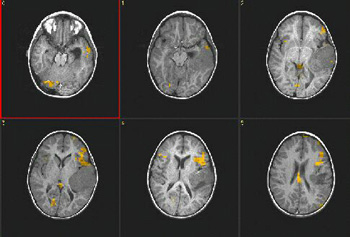

Caso 3

Paciente Paciente de sexo masculino de 14 años de edad, con convulsiones

Paradigma Tarea de dar golpecitos

ACTIVADO: Dar golpecitos con los dedos de forma alternada con la mano derecha

DESACTIVADO: No pensar en nada

Resultados La corteza del surco central izquierdo mostró una fuerte activación.  Las imágenes muestran claramente la relación con el tumor.

Comentarios El tumor se extirpó sin déficit motor postoperatorio.

Caso 4

Paciente Paciente de sexo masculino de 9 años de edad  con una lesión neoplásica en la fisura silviana izquierda.  Sin déficit del lenguaje

Paradigma Tarea de fluidez verbal

ACTIVADO: Pensar en acciones relacionadas con los sustantivos dados

Resultados Predominio obvio del lenguaje del lado izquierdo.  El área de Broca está bien definida junto con la circunvolución frontal superior izquierda.  Se ha descrito la asociación de la activación del cerebelo derecho con las tareas relacionadas con el lenguaje expresivo.